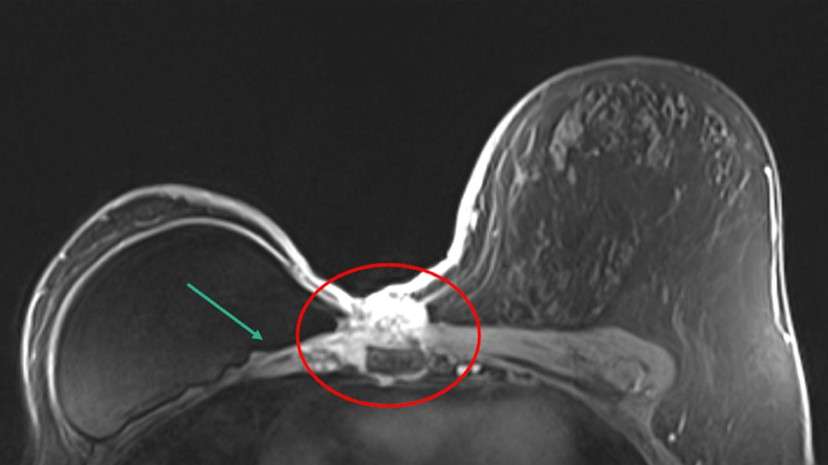

Case 1: Patient presented with a palpable right breast lump. Patient underwent diagnostic MRI which demonstrated the following (Figure 2).

Case: Chest Wall Invasion Figure 2

Figure 2: Bilateral breast MRI a, b) T1 post-contrast images show an enhancing round mass with irregular margins (red circle). There is non-mass-like enhancement extending from this mass posteriorly with direct invasion of the chest wall (blue circle). There is enhancement of the pectoralis major muscle (yellow arrow) and right intercostal muscles (green arrow). There is circumferential enhancement of underlying right parietal pleura (orange arrow).

This patient was diagnosed with triple negative invasive ductal carcinoma. Due to extent of disease, patient was treated with neoadjuvant chemotherapy.